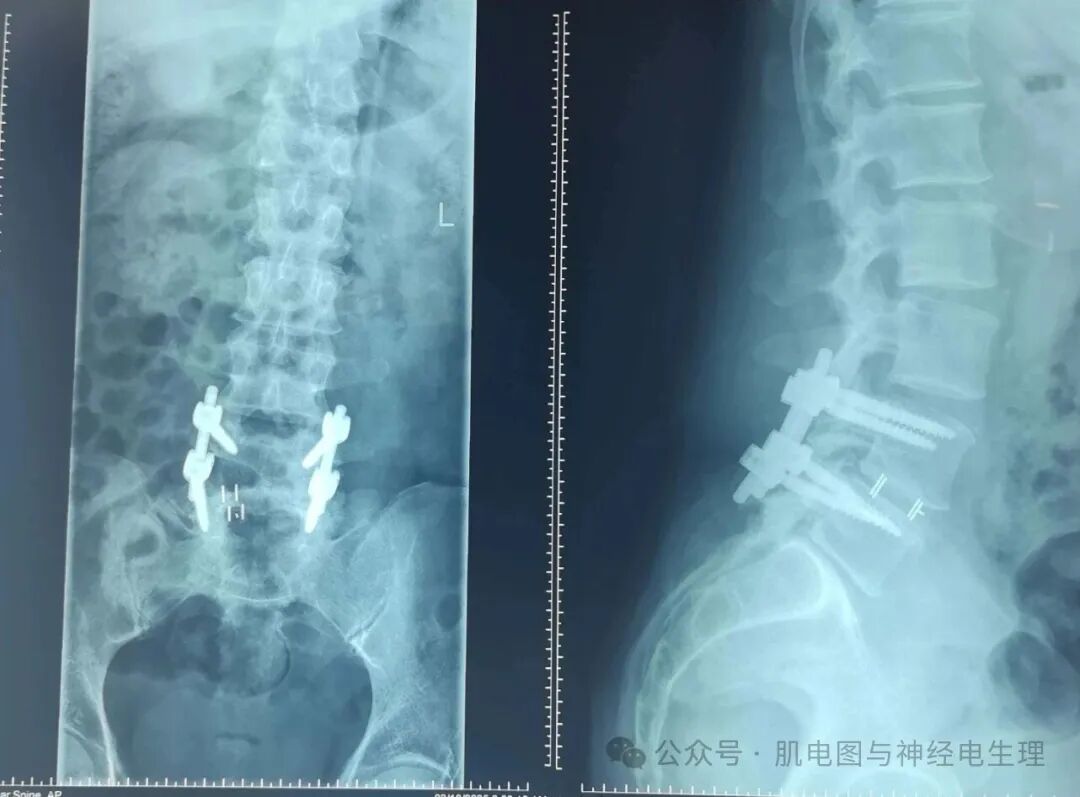

腰椎X片